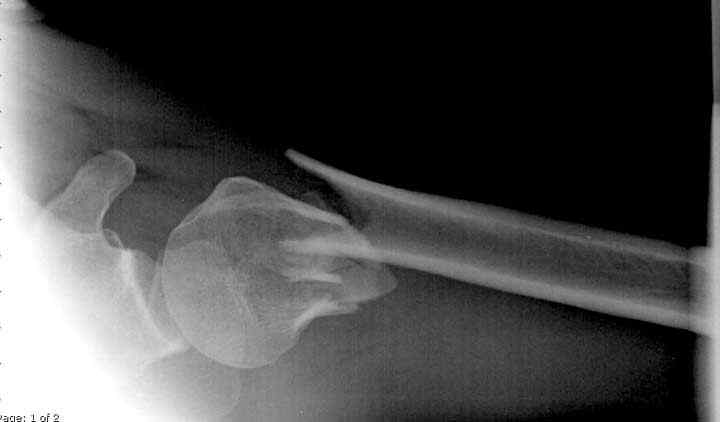

Здесь пример открытой репозиции 57 летнего с переломом плеча (1,2) смещение обнаружено на интероперационном снимке. При нормальной прямой проекция (3) угловое смещение обнаружили в аксиальной проекции (4)

После устранения смещения пластина установлена выше (5,6,7) и финальные снимки (8,9,10)

дополнительные снимки по протезированию